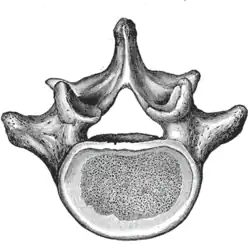

Der Wirbelbogen (Arcus vertebrae, Syn. Neuralbogen) ist ein paariger, bogenförmiger und dorsaler (rückenwärts ausgerichteter) Auswuchs eines Wirbels. Er beginnt mit einem „Füßchen“ (Pediculus arcus vertebrae), die sich in der Bogenplatte (Lamina arcus vertebrae) vereinigen. Zwischen dem Wirbelbogen und dem Wirbelkörper befindet sich das Wirbelloch (Foramen vertebrale), welches zusammen mit den Wirbellöchern der übrigen Wirbel den Wirbelkanal bildet, in dem das Rückenmark liegt. Der Wirbelbogen ist knorpelig oder knöchern.

Vom Wirbelbogen gehen verschiedene Fortsätze aus: Dorsal (rückenwärts) sitzt der Dornfortsatz (Processus spinosus oder Neurapophyse). Seitlich an den Wirbelbögen gelegen sind die Querfortsätze (Processus transversus oder Diapophyse), an denen – bei Säugetieren nur an den Brustwirbeln – die Rippen ansetzen. Bei manchen Fischen und den Landwirbeltieren (Tetrapoda) sind die Wirbelbögen durch die vier Gelenkfortsätze (Processus articulares oder Zygapophysen) miteinander verbunden, die sich auf der Vorderseite (Präzygapophysen) und der Rückseite (Postzygapophysen) der Wirbelbögen befinden. In der Schwanzwirbelsäule verschwinden die Wirbelbögen.